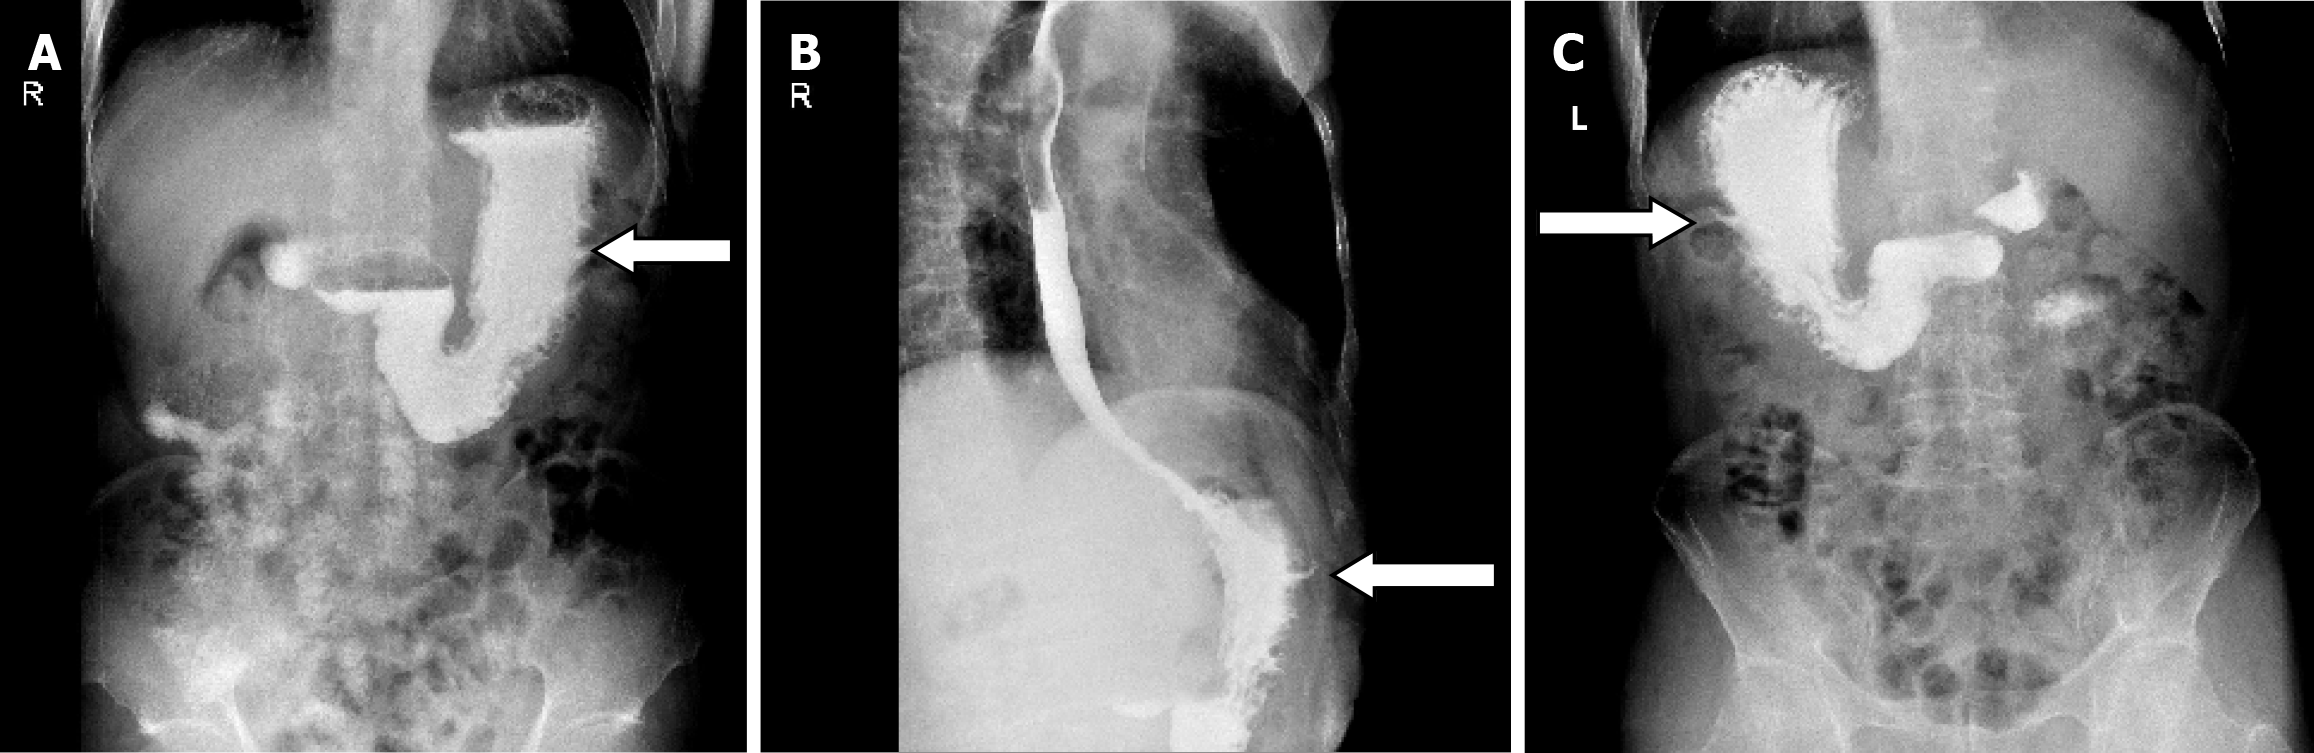

Laboratory and imaging examinations: The laboratory data obtained on this admission revealed a hemoglobin of 117

Diagnosis and treatment: According to the results of the abovementioned examinations, we unexpectedly determined the presence of a gastro-abdominal fistula. Its internal opening was in the greater curvature of the stomach body and the initial unhealed rupture on the left upper abdomen may be the external opening. As the incision on the adjacent left chest wall had not healed either and rib destruction was shown on the CT scan, we suspected an associated sinus in the chest wall. Unfortunately, although all available examinations including oral methylene blue and trans-sinus radiography had been performed, how it went through the abdominal wall as well as adjacent chest wall and whether branches remained was uncertain, which directly affected treatment. Following the exclusion of gastric malignancy, most doctors recommended an exploratory laparotomy, and the surgeons advocated gastric fistula drainage and gradual replacement of drainage tubes of smaller diameter until healed. We strongly recommended a thorough exploratory laparotomy, but the patient and his family chose gastric fistula drainage due to the fear of more invasive surgery.

On April 17, 2020, we performed trans-abdominal wall gastric fistula drainage and debridement of the chest sinus. In detail, we carefully explored inside via the left upper abdominal rupture using a blunt drainage tube with an appropriate diameter until the breakthrough was felt, and the tail end of the tube was inserted into a syringe. When withdrawing the syringe, viscous gastric juice was collected which demonstrated the formation of a gastric-abdominal fistula. During exploration through the unhealed incision on the adjacent chest wall, this revealed the existence of a chest sinus up to the ribs and intercostal muscles, but no communication with the stomach. This indicated that non-healing of the chest wall incision may be the result of broken ribs forming a sinus in the chest wall. The sinus tract was scratched with a spoon and the tissue was retained for pathological examination.